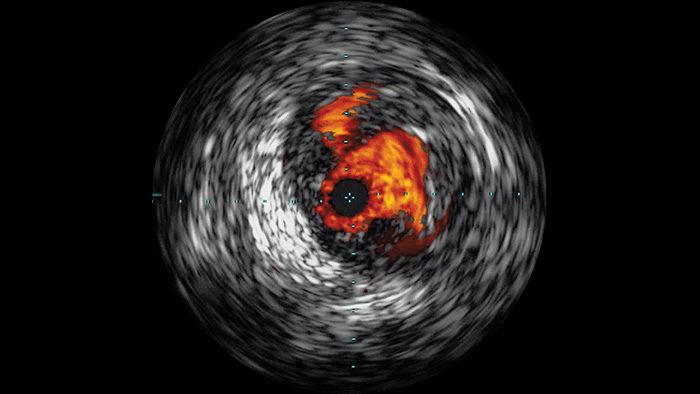

O ultrassom intravascular (IVUS) é uma tecnologia de diagnóstico por imagem baseada em cateter que permite que os médicos visualizem vasos sanguíneos de dentro para fora para ajudar na avaliação da presença e extensão de doenças. O IVUS ajuda a decidir, orientar e confirmar o tratamento intervencionista certo para cada paciente.

Visualiza imagens de vasos de alta definição com detalhes vasculares excepcionais, como apoio a estratégias precisas de tratamento, navegação e acompanhamento.